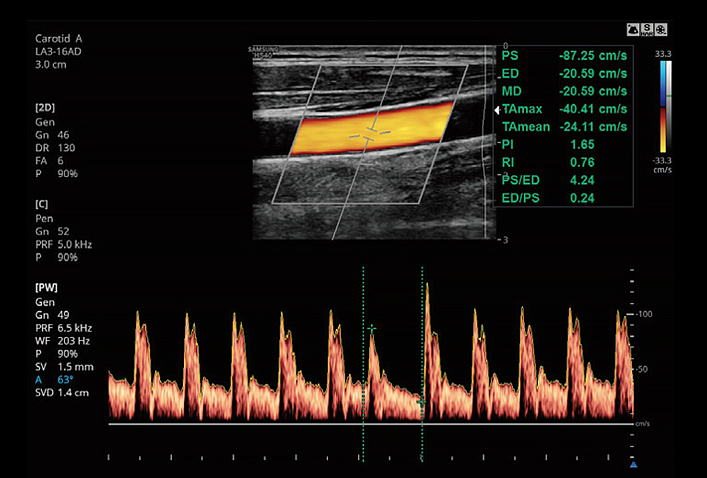

AutoIMT+ is a screening tool to analyze a patient's potential risk of cardiovascular disease. It allows easy intima-media thickness measurement of both the anterior and posterior wall of the common carotid by the click of a button.